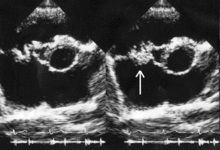

![]() Вегетации митрального клапана при инфекционном эндокардите. | |

Важное условие развития ИЭ — повреждение эндокарда или эндотелия, которое может возникать в результате пороков клапанов, микротравм, операции, проникновения инородных тел и др. К повреждённому эндотелию прикрепляются тромбоциты, образуется небольшой, первоначально стерильный тромб. Затем такой тромб инфицируется различными возбудителями, циркулирующими в крови. Таким образом формируется вегетация, состоящая из бактерий, фибрина, лейкоцитов и тканевого детрита. Вегетация — характерный признак ИЭ, обнаруживаемый при эхокардиоскопии. Сами бактерии также способны напрямую повреждать клапаны сердца с образованием различных дефектов, фистул и абсцессов.

Окончательный диагноз устанавливают при получении положительных результатов посева крови и данных об обнаружении вегетаций при эхокардиографии.

Среди различных визуализирующих исследований методом выбора считают ЭхоКГ. Её результаты служат основой для дальнейшего ведения пациента. Доказано, что в отношении выявления вегетаций, деструктивных осложнений и абсцессов транспищеводная ЭхоКГ обладает большей чувствительностью по сравнению с трансторакальной ЭхоКГ . При серьёзных клинических подозрениях на эндокардит и неубедительных или отрицательных данных трансторакальной ЭхоКГ следует проводить транспищеводное исследование. Напротив, отрицательные данные транспищеводной ЭхоКГ в значительной степени ставят под сомнение диагноз ИЭ. Тем не менее при сохранении существенных клинических признаков (например, при положительном посеве крови и выделении типичного возбудителя) транспищеводную ЭхоКГ следует повторить через несколько дней, особенно при наличии предрасполагающих заболеваний сердца (например, при протезе клапана сердца). Показано, что отрицательные результаты повторной транспищеводной ЭхоКГ характеризуются высокой отрицательной прогностической ценностью в отношении ИЭ и могут служить «золотым стандартом» для исключения диагноза ИЭ. В связи с увеличением частоты распространенности предшествующего лечения антибиотиками, приводящего к получению ложноотрицательных посевов крови, и эндокардита протезов клапанов, затрудняющего визуализацию вегетаций, было предложено модифицировать критерии Дьюка. Модификация подразумевает включение в эту систему пациентов с отчетливыми вегетациями (по данным ЭхоКГ) и признаками системного воспаления, но с отрицательными результатами посевов крови, при условии, что они ранее получали антибактериальную терапию. Кроме того, добавлено требование исключать эндокардит у пациентов с протезами клапанов на основании повторного получения отрицательных результатов транспищеводной ЭхоКГ. Более того, для исключения эндокардита на фоне ку-лихорадки следует рутинно применять серологические методы, поскольку при этом заболевании микроорганизмы из крови не выделяют.